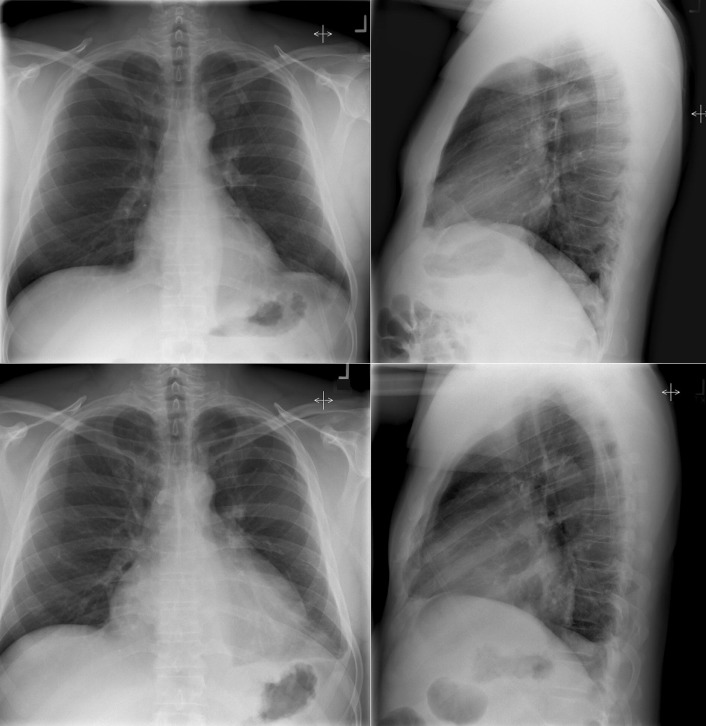

Constrictive Pericarditis

In constrictive pericarditis ( Graphic 16-1 ; Figs. 16-16 to 16-23 ) , the CPS is usually nonspecifically and mildly enlarged. Occasionally, the heart is normal or small in size. The left atrium is the most frequently enlarged chamber, because its enlargement is less restricted by pericardium. The right atrial contour on the frontal chest radiograph may be flattened. Calcification of the pericardium suggests past tuberculosis, but since tuberculosis has become uncommon at most centers, 90% of cases of constrictive pericarditis are currently noncalcified. Calcification, especially diaphragmatic, is not specific for constrictive physiology; it may be seen in the absence of cardiac compression. The apical surface is less frequently calcified than the interventricular and atrioventricular grooves. The apex seldom calcifies prominently in constrictive pericarditis; this finding suggests a calcified apical aneurysm rather that constrictive pericarditis.